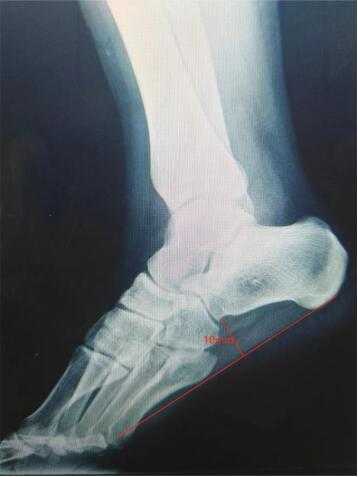

3.5. 治疗前和治疗1年后随访3组患者X线检查结果比较

X线检查结果显示,3组患者治疗前的足弓均有不同程度的形变甚至消失,部分患者跖筋膜起点处已长出骨刺;治疗1年后3组患者的足弓均有不同程度的恢复,如图2。可见足弓高度增加4 mm,足弓功能得到恢复。

Figure 2. Comparison before and after 1 year of treatment

2. 治疗1年前后对比